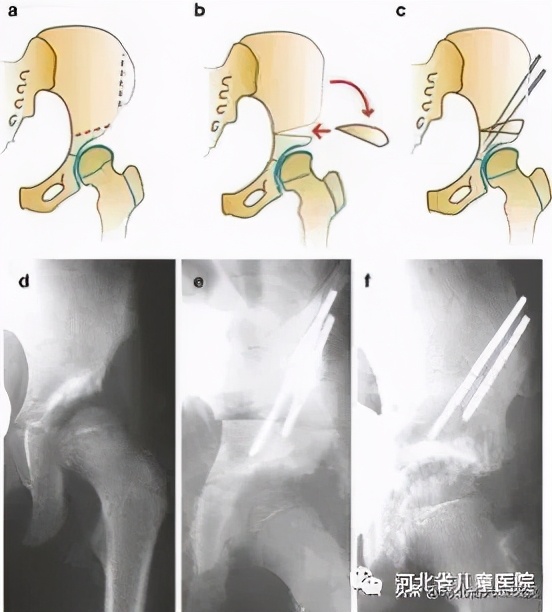

2岁及2岁以上

该年龄段,孩子的股骨头可能处于更高位,肌肉挛缩可能更严重,需要经前期的牵引之后,行切开复位骨盆截骨,在切开复位同时,视情况行股骨的短缩旋转截骨。